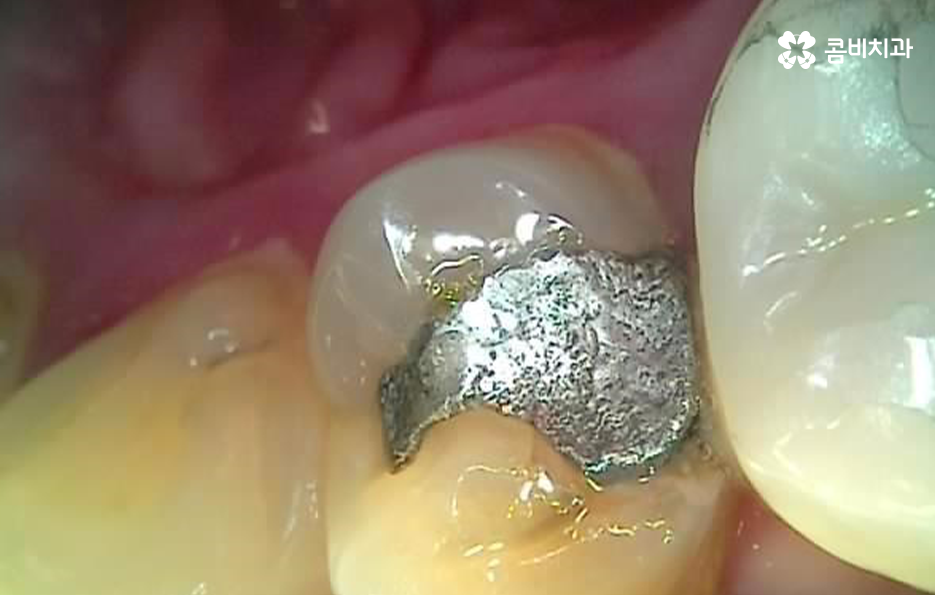

하지만 성인들의 충치 치료는 위 사례들처럼 과거 오래전에 치료 했던 아말감이나 보철물이 떨어지기도 하고 접착제가 약해지면서 2차 충치가 내부에서 진행되어 보철물을 제거하고 내부 상태를 파악해야 하는 경우가 자주 발생되고 있는데요

크고 작은 보철치료를 하다 보면 보철물의 수명이 다하고 교체를 해야하는 시점이 찾아오게 되는데 보철물 내부에서 발생될 수 있는 2차 충치는 기본적으로 주기적으로 검진하지 않고 통증이나 특정 불편함으로 인해 치과에 방문하게 되시면 치료의 적기를 놓치는 경우가 많다고 볼 수 있어요

또한 치료는 보기 좋게 레진으로 교체 치료가 가능하다고 해도 어금니 처럼 압력을 강하게 받는 치아 부위의 경우 혹은 치아의 홈 부분이 아니라 옆면 치료를 해야 하는 경우에는 당장의 치료 결과만이 아니라 치료 후 유지와 지속성에 대해서도 고려해야 하기 때문에 레진으로 치료가 가능하더라도 금방 레진이 깨지거나 탈락우려가 높다면 인레이 치료나 크라운 치료를 하게 되는 경우가 발생될 수 있어요